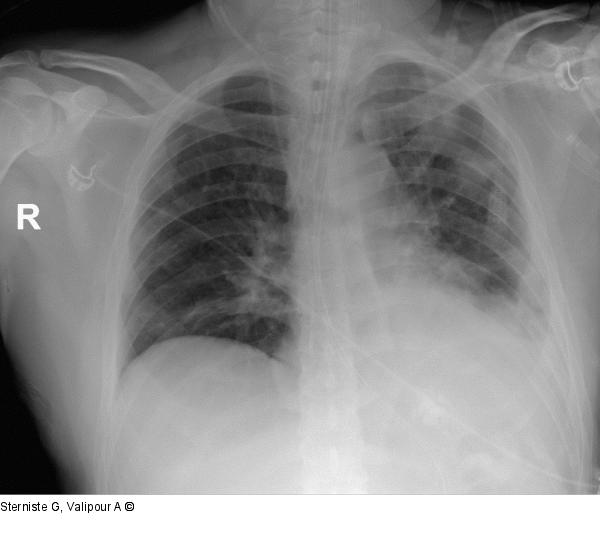

Abbildung 2: Thoraxröntgen

Thoraxröntgen 27.02.2022